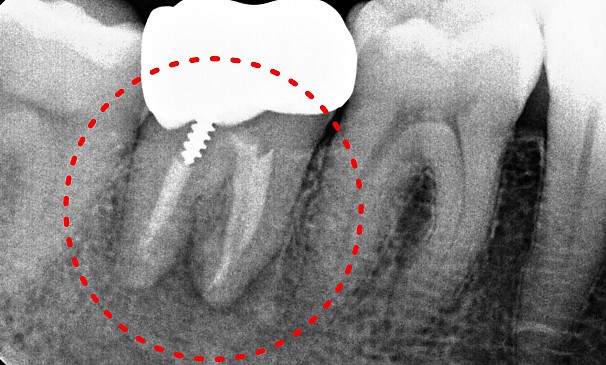

치아살리기 치료

자연치아를 최대한 살려

오래 쓸 수 있도록 최선을 다합니다.

자연치아를 최대한 살려

오래 쓸 수 있도록 최선을 다합니다.

치아살리기 치료